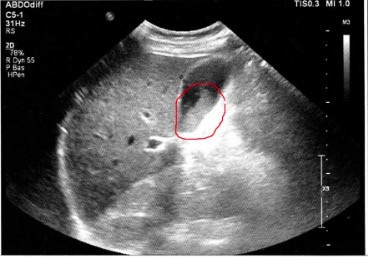

Examen échographique : ci dessous, je montre 2 images d'échographie avant et après nettoyage de la vésicule biliaire, confirmant qu'il y a eu expulsion des calculs biliaires grâce à la cure d'Andreas Moritz. Ces images sont tirées des témoignages de personnes ayant pratiqué cette cure.

- Vous faîtes une échographie de contrôle juste après la cure : la vésicule ne contient plus de calculs ou en contient moins. Le médecin en profite pour vérifier la paroi de la vésicule.